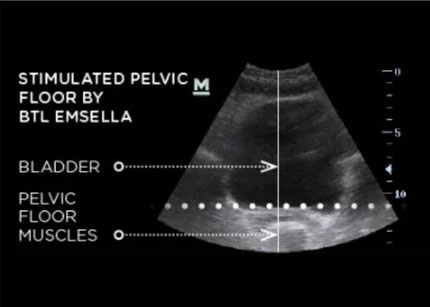

The Emsella Chair is an FDA-cleared device that strengthens pelvic floor muscles using high-intensity focused electromagnetic energy (HIFEM). You sit on the chair fully clothed for 30 minutes. The device triggers thousands of deep pelvic floor contractions per session, training muscles that most people can't activate on their own.

The Emsella triggers contractions at an intensity you can't achieve voluntarily. 11,000 contractions per session retrains the entire pelvic floor musculature.